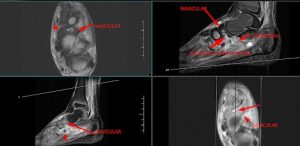

Compressed navicular bone, demonstrate diffuse low intensity with a central ovoid abnormal STIR hyperintensity with internal low intensity rim which is communicating with large surrounding inferior perinavicular collection through a inferior cortical defect – represents osteonecrosis of the navicular bone (Köhler disease ) with secondary osteomyelitis.

Thin fluid collections surrounding the tibialis posterior, flexor digitorum longus and flexor hallucis longus tendons associated with ankle joint effusion – suggestive of infective tenosynovitis.